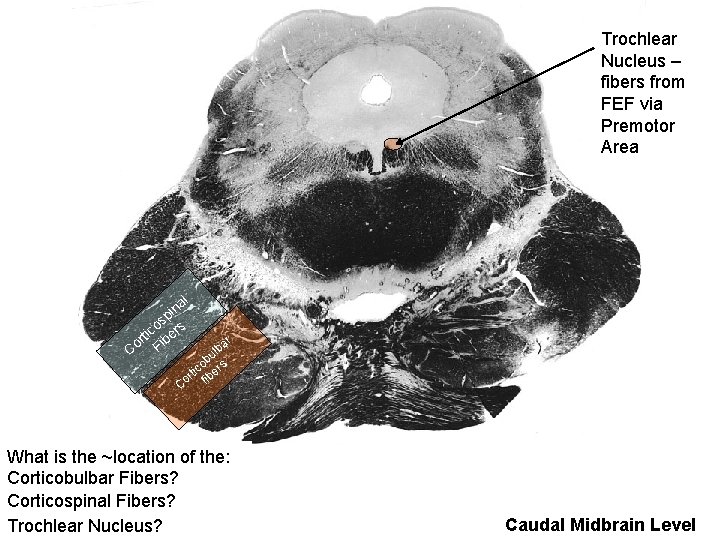

Trochlear Nucleus – fibers from FEF via Premotor Area al n i sp s o tic iber r Co F ar lb u ob s tic ber r i Co f What is the ~location of the: Corticobulbar Fibers? Corticospinal Fibers? Trochlear Nucleus? Caudal Midbrain Level